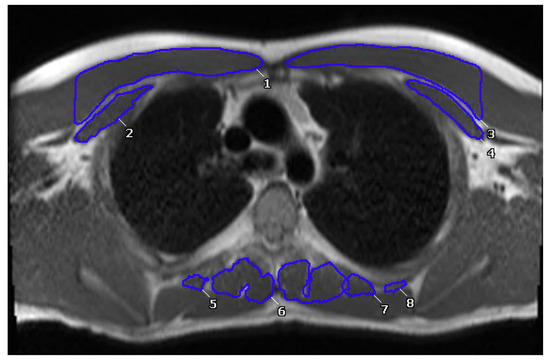

Muscle measurements were obtained by analyzing each patient’s most recent CMR. The skeletal muscle area (SMA) of the patients was assessed in the axial view on bright blood bSSFP static images at the level of Carina with offline analysis software (Cvi-42, Circle Cardiovascular Imaging Inc., Calgary, AB, Canada). Measurements of muscle area were conducted in images in static SSFP axial stack. The pectoralis major and minor muscles were traced for the assessment of anterior muscle area, while the paraspinal muscles were traced for posterior muscle area at the level of T4 (Figure 1) [29]. Due to the large variation in height and body habitus of our cohort, SMA, which is reported in cm2, was indexed by body surface area (BSA) by using the Mosteller calculation [30]. BSA-indexed SMA was reported as cm2/m2. Due to a lack of standardized values that matched our baseline characteristics in a non-Fontan population, we divided patients into high- and low-muscle groups, with high being the upper 25th percentile and low being the lower 25th percentile for BSA-indexed SMA.

Figure 1.

Segmentation of anterior and posterior paraspinal muscles at the level of the carina. Numbers seen on scan signify different hand traced muscles to quantify total muscle area of anterior and posterior muscles.